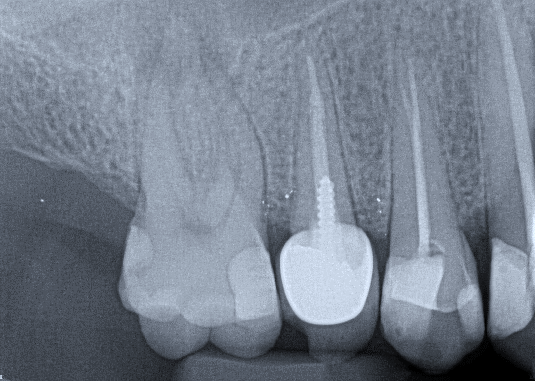

1. (Select ONE OR MORE correct answers)

Which of the following may complicate the extraction of tooth 3.5?

6. Select ONE OR MORE correct answers)

Which of the following may complicate the extraction of tooth 1.5?

11. (Select ONE OR MORE correct answers.)

Which of the following may complicate the extraction of tooth 4.5?

14. (Select ONE OR MORE correct answers.)

Which of the following may complicate the extraction of tooth 2.5?

16. (Select ONE OR MORE correct answers.)

Tooth 1.8 is planned for surgical extraction. Which radiographic findings suggest an increase in the degree of difficulty of the extraction?

18. Select ONE OR MORE correct answers.)

Tooth 2.8 is planned for surgical extraction. Which radiographic findings suggest an increase in the degree of difficulty of the extraction?

20. (Select ONE OR MORE correct answers.)

Which of the following may complicate the surgical extraction of tooth 1.6?

21. (Select ONE OR MORE correct answers.)

Which of the following may complicate the extraction of tooth 4.6?

22. (Select ONE OR MORE correct answers.)

Tooth 1.6 is planned for extraction. Which are the most likely postoperative complications?

23. Select ONE OR MORE correct answers)

Which of the following may complicate the extraction of tooth 1.4?

25. (Select ONE OR MORE correct answers.)

Tooth 4.8 is planned for extraction. Which radiographic findings suggest an increase in the degree of difficulty of the extraction?